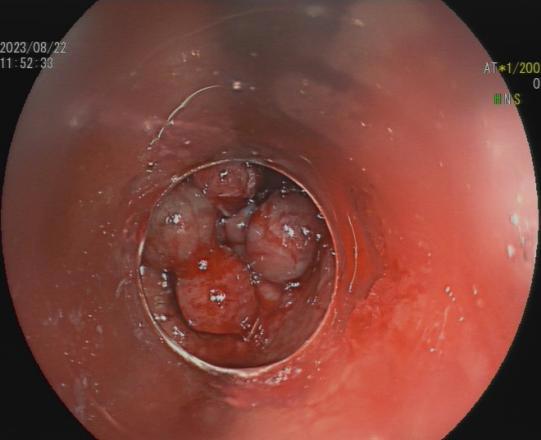

8.内镜下内痔硬化剂及套扎治疗

内镜套扎治疗及硬化治疗 适合I-III期 内痔,包括部分混合痔的微创治疗,疗效显著,与传统外科手术相比,超级微创、费用低、见效快,具有很大优势。

III度内痔 硬化剂及套扎术后